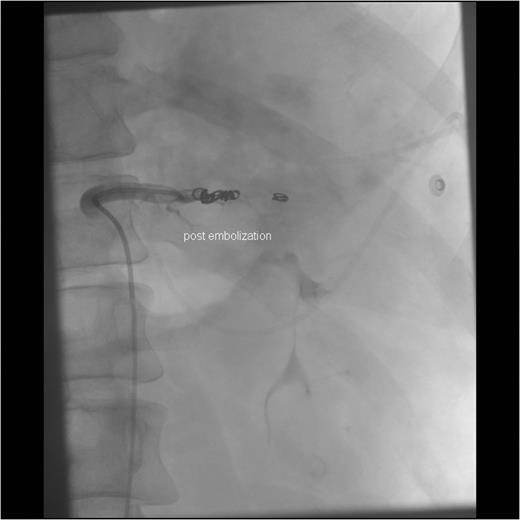

Angiographic imaging post-embolization observing four proximal coils in the splenic artery 3–4 cm distal to the celiac trunk.